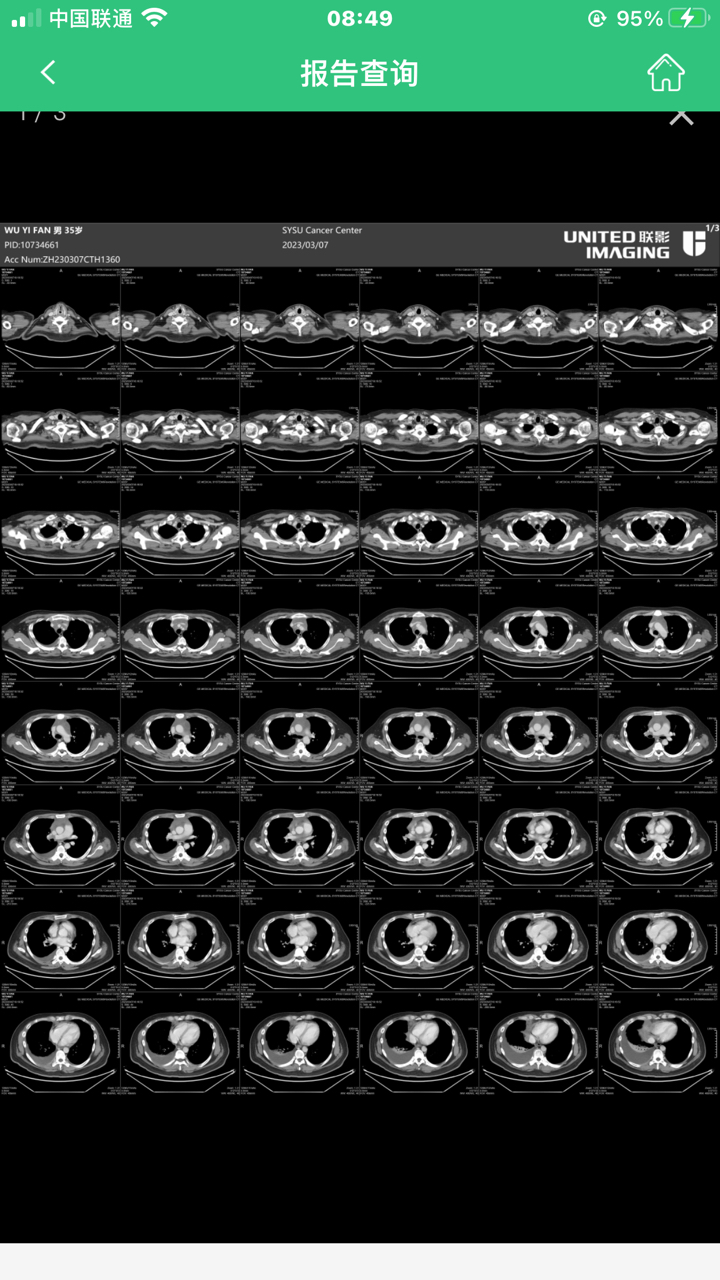

求指点第二次加强平扫ct,是好转还是怎样?

由确诊到救治,第二次加强平扫ct,是好转还是怎样?求指点

请问一下这个CT全名叫啥我们也要做不过不在中肿